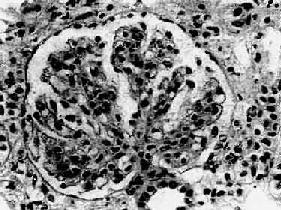

图12-7 弥漫性毛细血管内增生性肾小球肾炎

肾小球内细胞数量增多,系膜细胞和内皮细胞增生并有少量中性白细胞浸润,毛血管腔狭窄